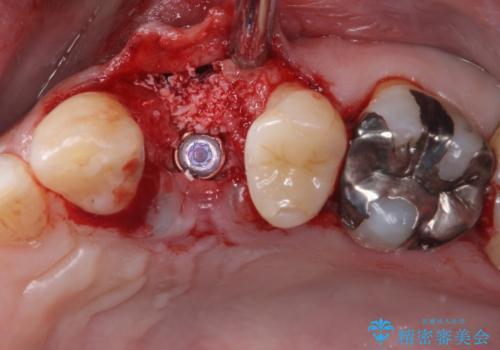

割れてしまった小臼歯 インプラントによる補綴治療

- 他院で抜歯が必要と診断され、再度診断を希望して来院された患者様です。

顕微鏡下で診察を行ったところ、歯根が垂直に破折していたため、抜糸してインプラントによる補綴治療を行うこととしました。

インプラントは、人工骨を用いた際の骨誘導能が比較的高いとさせるストローマン社のSLActiveを使用しました。